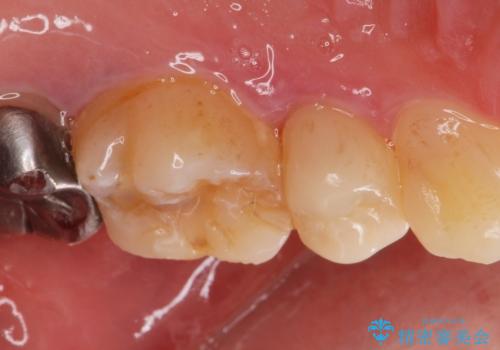

- 他院で被せた保険の白い被せ物(樹脂)をセラミックの被せ物に変えたいとの事で来院。

被せ物を外し、虫歯がないことを確認してセラミックの被せ物(ジルコニアクラウン)の治療を行いました。